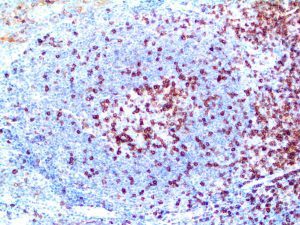

It is the ICU physician who is most likely to witness one of the deadliest manifestations of the abnormal immunological response, the cytokine storm syndrome (CSS). This response is also referred to by some as the cytokine release syndrome (CRS). CSS is characterized by continuous activation and expansion of macrophage and lymphocyte populations, which secrete large amounts of cytokines, causing the cytokine storm. This massive cytokine release is akin to hemophagocytic lymphohistiocytosis (HLH) disease, a syndrome characterized by initial unchecked and persistent activation of cytotoxic T lymphocytes and NK cells.

Clinical and laboratory manifestations of HLH include fever, enlarged liver and/or spleen, neurologic dysfunction, coagulopathy, liver dysfunction, cytopenias (i.e., low levels of erythrocytes, leukocytes, and/or platelets), hypertriglyceridemia, hyperferritinemia, hemophagocytosis, and eventually diminished NK cell activity as the immune system becomes progressively paralyzed. HLH can be familial (primary HLH) or secondary to another disease process (sHLH), such as rheumatic disease, in which it is referred to as macrophage activation syndrome (MAS, characterized by elevated ferritin).